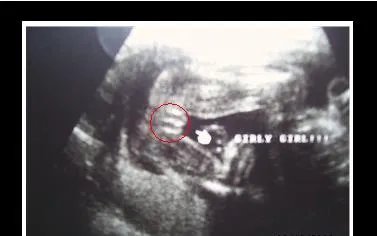

首先是女宝宝的, “三线” 是一个明显的标记: